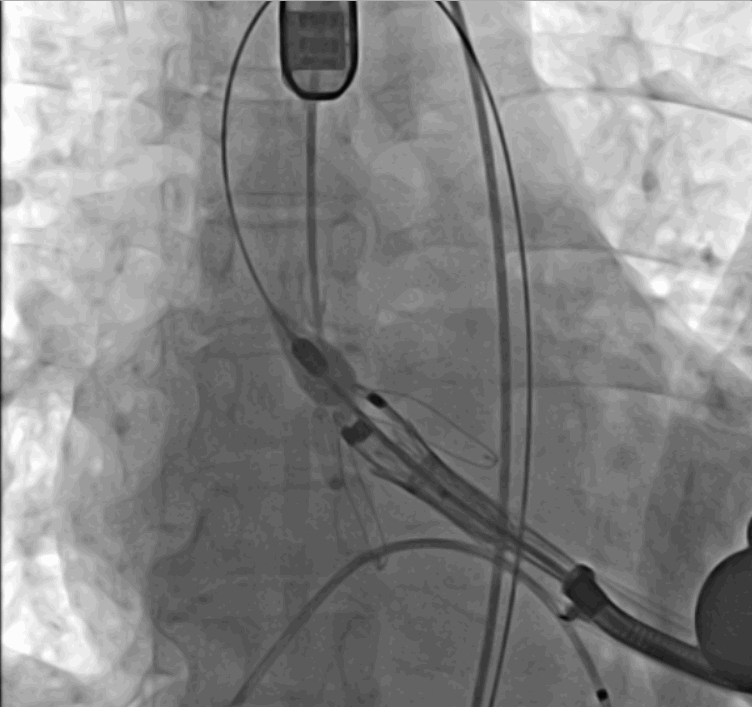

術前DSA影像圖

手術采用經心尖入路,對患者進行全麻后,在左側心尖處做3-4cm微創手術切口,在DSA及超聲引導下手術順利完成。從導入器械到完成瓣膜置入,僅耗時約10分鐘。術后即刻主動脈瓣返流程度由術前大量返流轉為消失,患者于導管室拔除氣管插管,次日由ICU轉入普通病房。